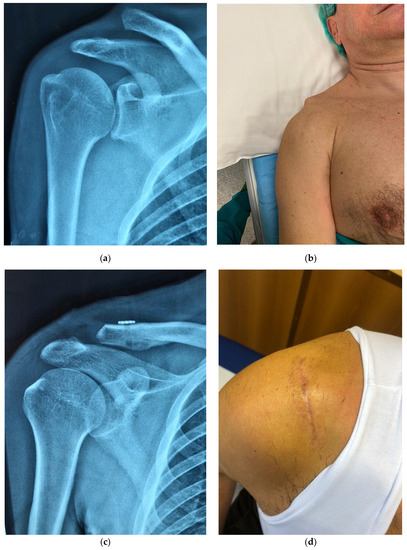

2. Material and Methods

2.1. Surgical Technique